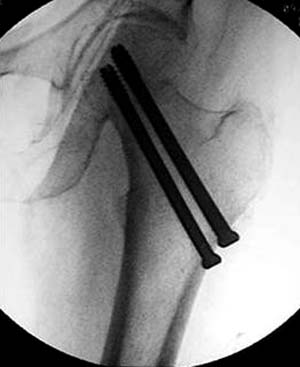

Уважаемые коллеги!Очень уважаемый наш коллега из далекой области по телефону отправил р-снимок своего брата, 43года, с переломом шейки бедра. Снимок не очень качественный, пока других нет,кажется перелом субкапитальный, линия излома косая, похоже В2,2 по АО,или Паувельс- 2,. Просит, если можно, чтобы наш форум помог советом, каким способом лечить брата.

результат, в конце операции.